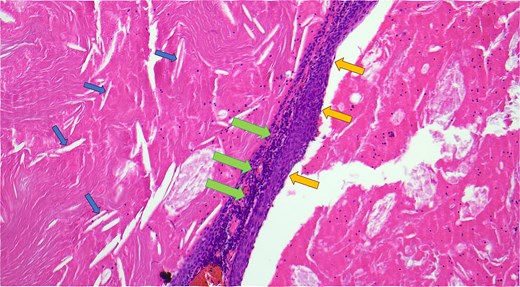

Haematoxylin and eosin-stained microscopic cross-sectional sample demonstrating numerous cholesterol clefts (small left arrows), a band-like rim of lymphocytes (middle large arrows), and the squamous epithelial lining of the cyst wall (medium right arrows).